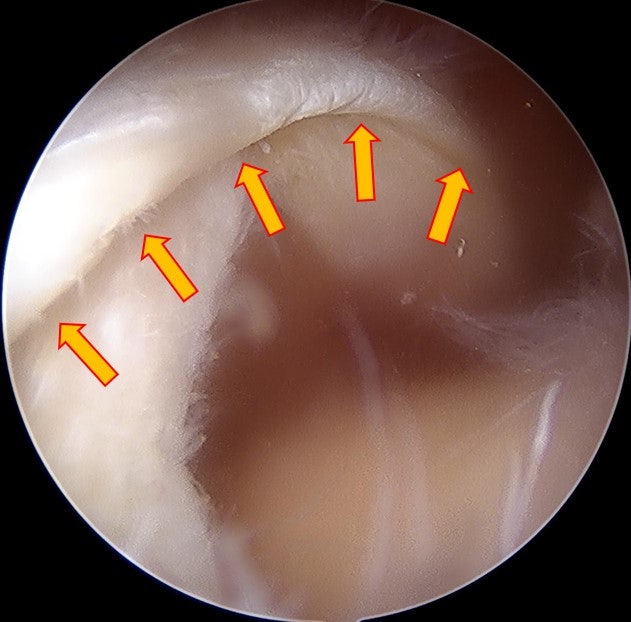

이학적 검사나 x-ray 소견상 회전근개 파열이 상당히 많이 의심되어 MRI 검사를 시행하였습니다.

이러한 경우 회전근개가 원래 상완골의 대결절까지 복원이 되어야 하는데 그렇게 되지 않을 가능성이 많습니다. 그래서 환자분의 수술 계획은 최대한 봉합술을 시행하고 복원되지 않는 부위는 인조인대(allomend)를 이용하여 보강하기로 계획하였습니다.